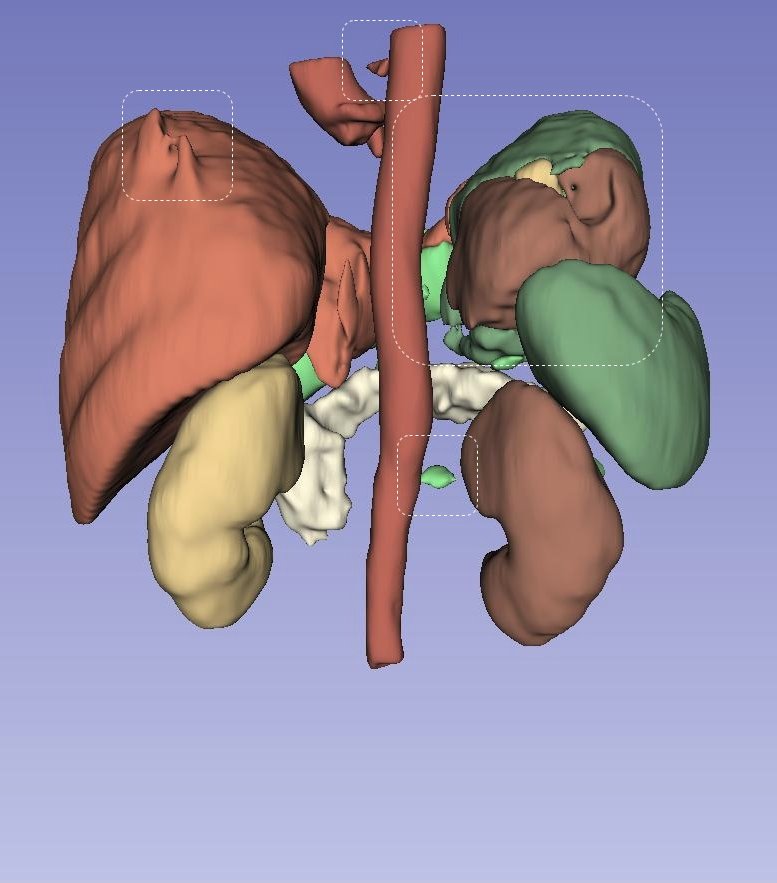

Left Atrial Dataset (LA): Figure˜5 presents a qualitative, three-dimensional visualization of various models’ performance in segmenting the Left Atrial dataset for individual patients. Each row in the figure is dedicated to the segmentation results from a single patient’s dataset, visually assessing each model’s predictive capabilities. In the case of the first patient, shown in the top row, all models except UNETR manage to generate a single entity segmentation, highlighting their ability to integrate disparate anatomical features into a unified model prediction. However, a common challenge across all models is the accurate segmentation of the right corner of the atrium, suggesting a shared area of potential improvement. For the second patient, delineated in the second row, it is discernible that competing models struggle to accurately segment the entirety of the ground truth, resulting in multiple segmented instances rather than a single cohesive structure. Contrarily, LHU-Net succeeds in rendering a single, contiguous segmentation that closely resembles the ground truth, demonstrating its ability to produce smoother and more coherent segmentations. The last patient, as illustrated in the bottom row, presents a challenging case where all models exhibit a tendency for over-segmentation at the base of the atrium. This is indicative of the intrinsic complexity of accurately delineating this anatomical region. Nevertheless, it is worth noting that certain models, specifically UNETR and SwinUNETR-V2, additionally exhibit under-segmentation in other areas, further complicating the segmentation task. In summation, the visualizations in Figure˜5 suggest that LHU-Net consistently generates more robust and smoother segmentations, avoiding the creation of extraneous entities.

NIH pancreas dataset (CT-82): Figure˜6 provides a three-dimensional visualization for the qualitative analysis of pancreatic segmentation across several state-of-the-art models. Each row visually represents the segmentation results from an individual patient’s dataset, offering insight into the predictive precision of each model. For the first patient, illustrated in the first row, it is observable that all models, except for LHU-Net, UNETR++, and SwinUNETR-v2, could not produce a singular, cohesive entity representing the organ. UNETR++ generates a single entity; however, it significantly under-segments the pancreas, failing to capture the complete anatomical structure. In stark contrast, LHU-Net achieves a segmentation that closely approximates the ground truth, underscoring its capability to preserve the organ’s integrity in the segmentation process. The second patient’s data, depicted in the second row, further accentuates the proficiency of LHU-Net in producing a smooth and robust segmentation, particularly when compared to its counterparts. Notably, UNETR++ exhibits a fragmentation in the segmentation, resulting in multiple entities and suggesting a lack of robustness within this dataset. The visualization of the third patient, in the third row, reveals the intrinsic challenges posed by this dataset, as all models predict multiple entities. Nonetheless, LHU-Net distinguishes itself by accurately segmenting the predominant portion that aligns with the ground truth and generating only a minor secondary entity. This contrasts with the other models, which produce multiple, larger erroneous segments, thus compromising the segmentation’s fidelity. Overall, LHU-Net demonstrates superior robustness and smoothness in its segmentation outputs, consistently predicting the pancreas with a higher degree of anatomical accuracy.